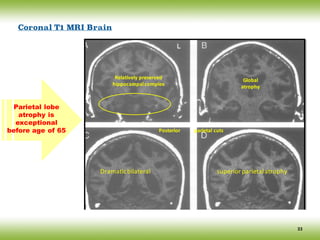

Relatively	preserved

hippocampal	complex

Global

atrophy

Posterior											parietal	cuts

Dramatic	bilateral																																											superior	parietal	atrophy

Coronal T1 MRI Brain

Parietal lobe

atrophy is

exceptional

before age of 65